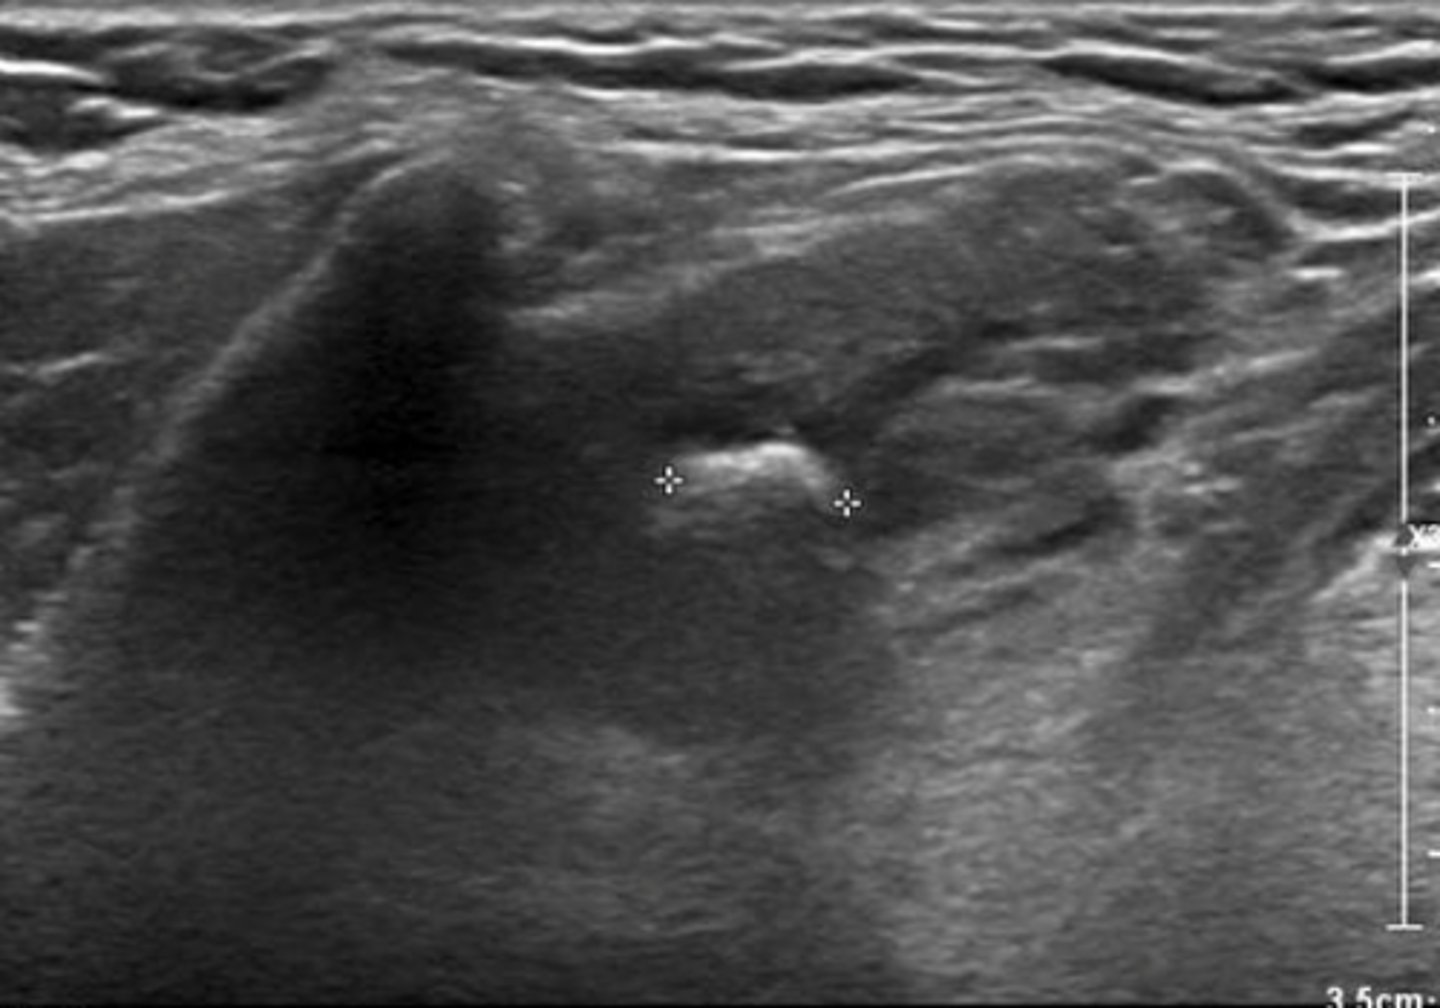

Cysts of the Neck - Brachial cleft cyst:

Etiology

-Congenital _____ of the brachial cleft

Clinical findings

-Asymptomatic

-Palpable _____ neck mass

Sonographic findings

-Anechoic _____ neck mass

-Located directly below the angle of the _____

-Located _____ to the SCM muscle

-May demonstrate internal _____

-Congenital diverticulum of the brachial cleft

-Palpable lateral neck mass

-Anechoic superficial neck mass

-Located directly below the angle of the mandible

-Located anterior to the SCM muscle

-May demonstrate internal debris